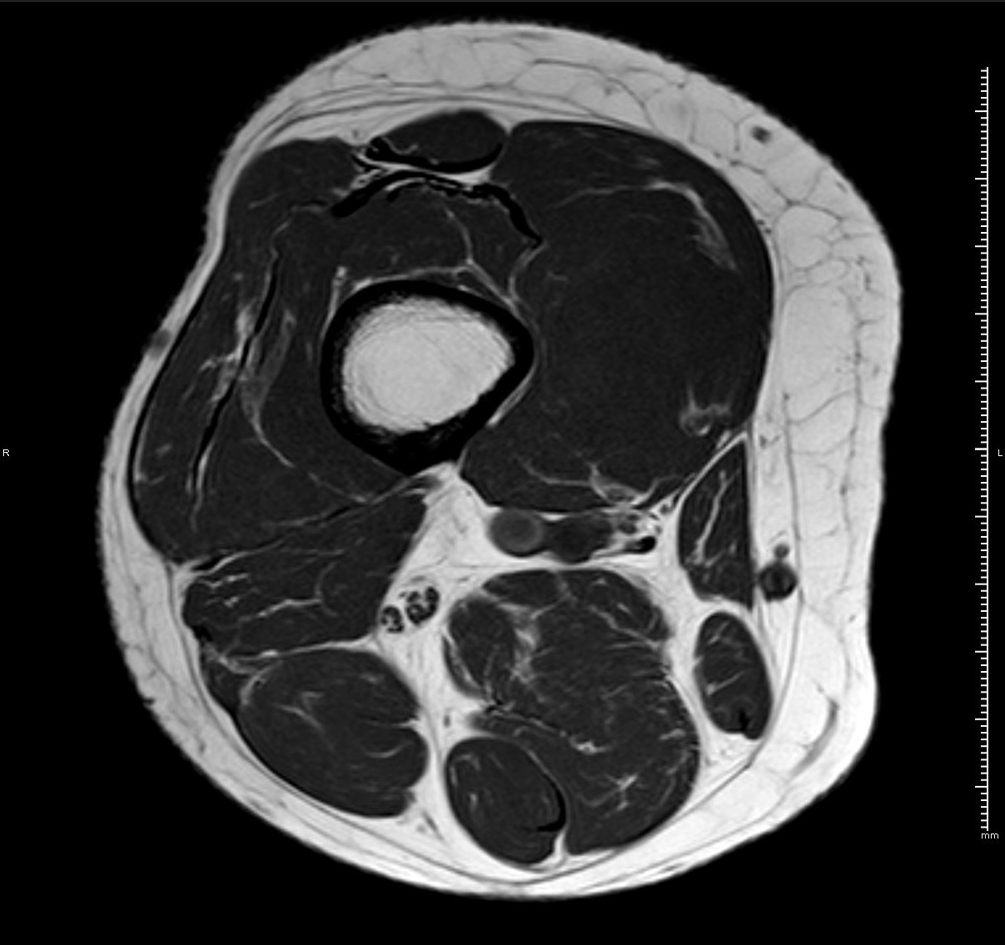

RM axial T1 con supresión grasa y gadolinio iv.

HALLAZGOS RADIOLÓGICOS